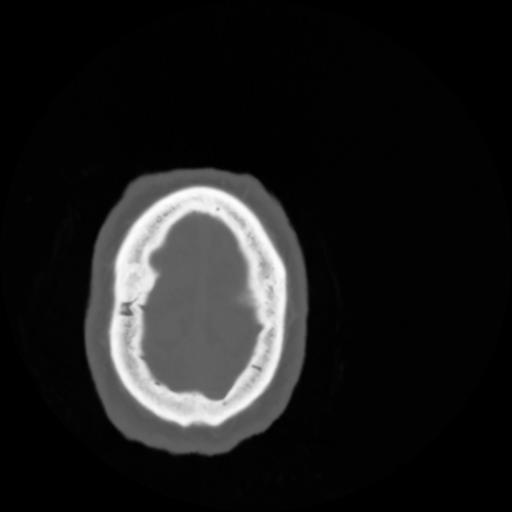

4 CEREBRO,,Vol,0.5,CEREBRO,,